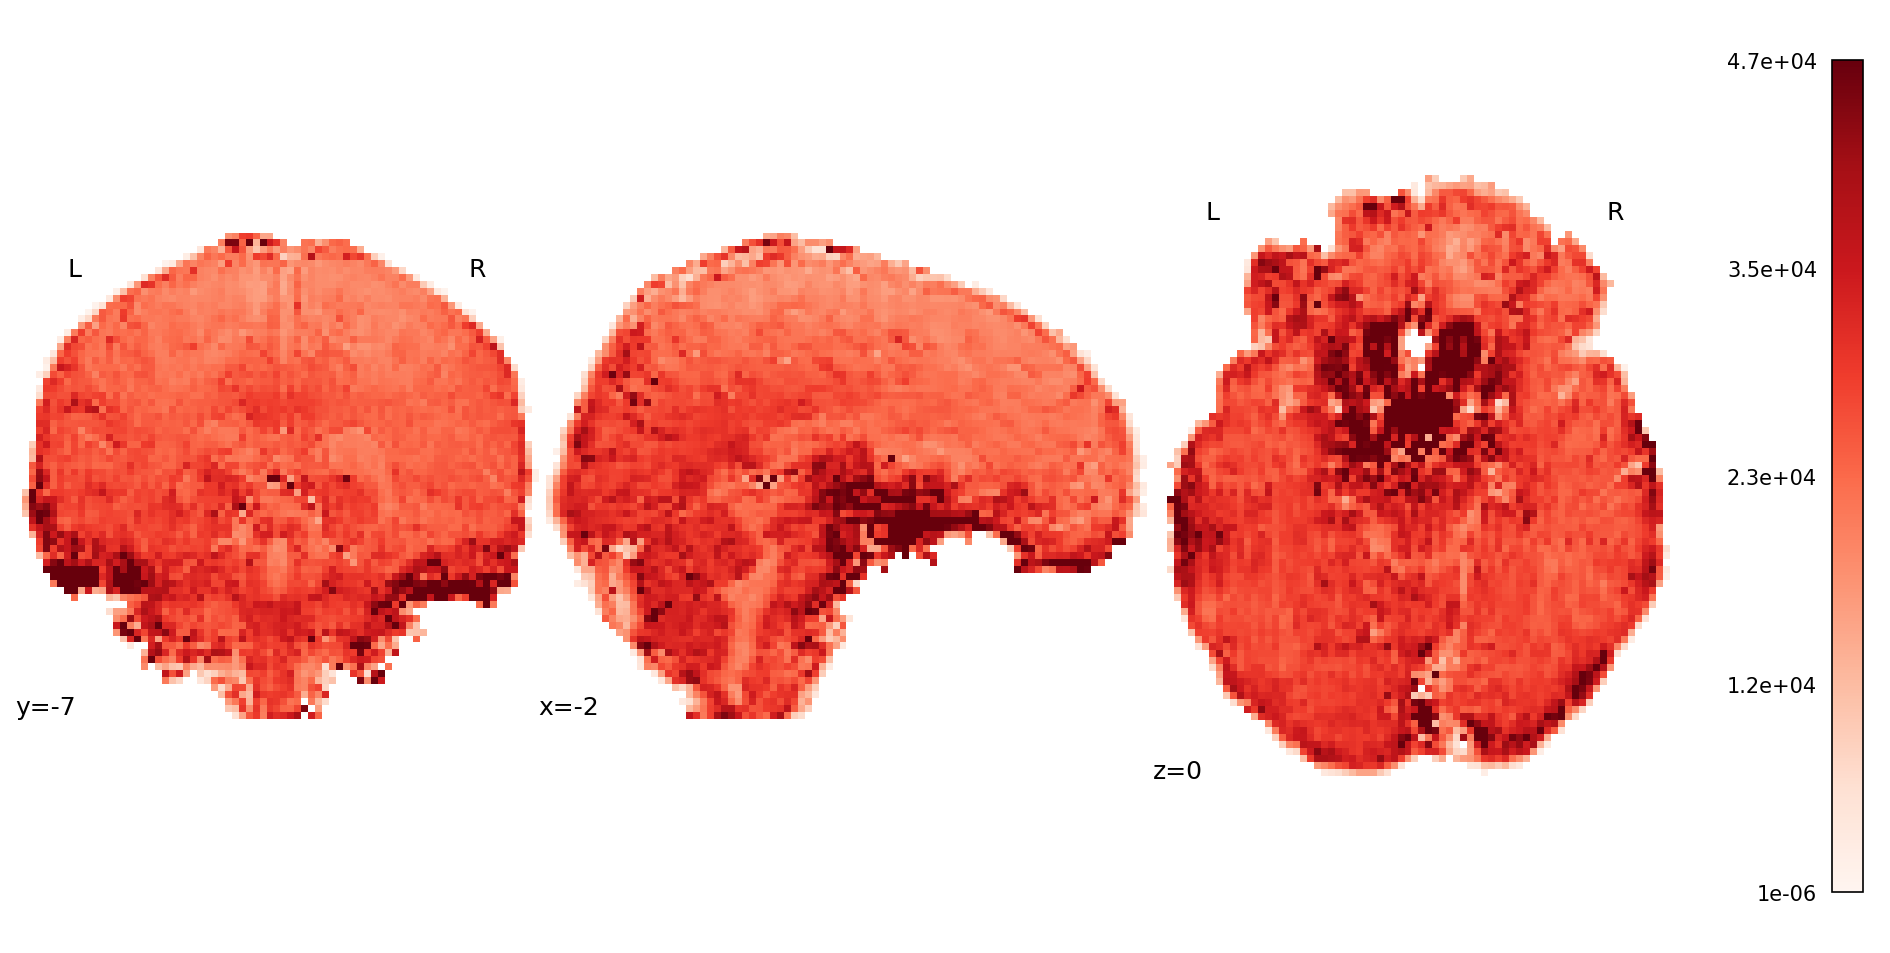

glue_figure("figure_mean_volumewise_t2s", fig, display=False)

../_images/5c085e64e8f7d4ce57a63aa9319ba1667122345e7c3ded39d223a791f33a66be.png

Fig. 29 Mean map from the volume-wise T2* estimation.#